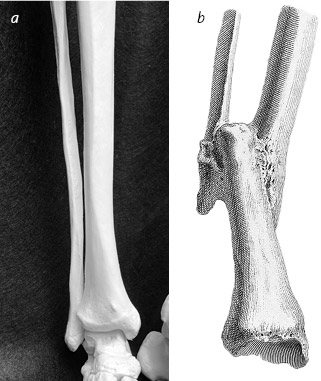

Иллюстрация к книге — Кости: внутри и снаружи [i_021.jpg]

Правильная форма и расположение костей голени (a) резко отличаются от состояния после перелома (b). Раньше успехом считали даже такое заживление, после которого нога становилась короткой и деформированной, а человек хромал

William Cheselden, Osteographia, or the Anatomy of the Bones (London: W. Bowyer, 1733) (b)